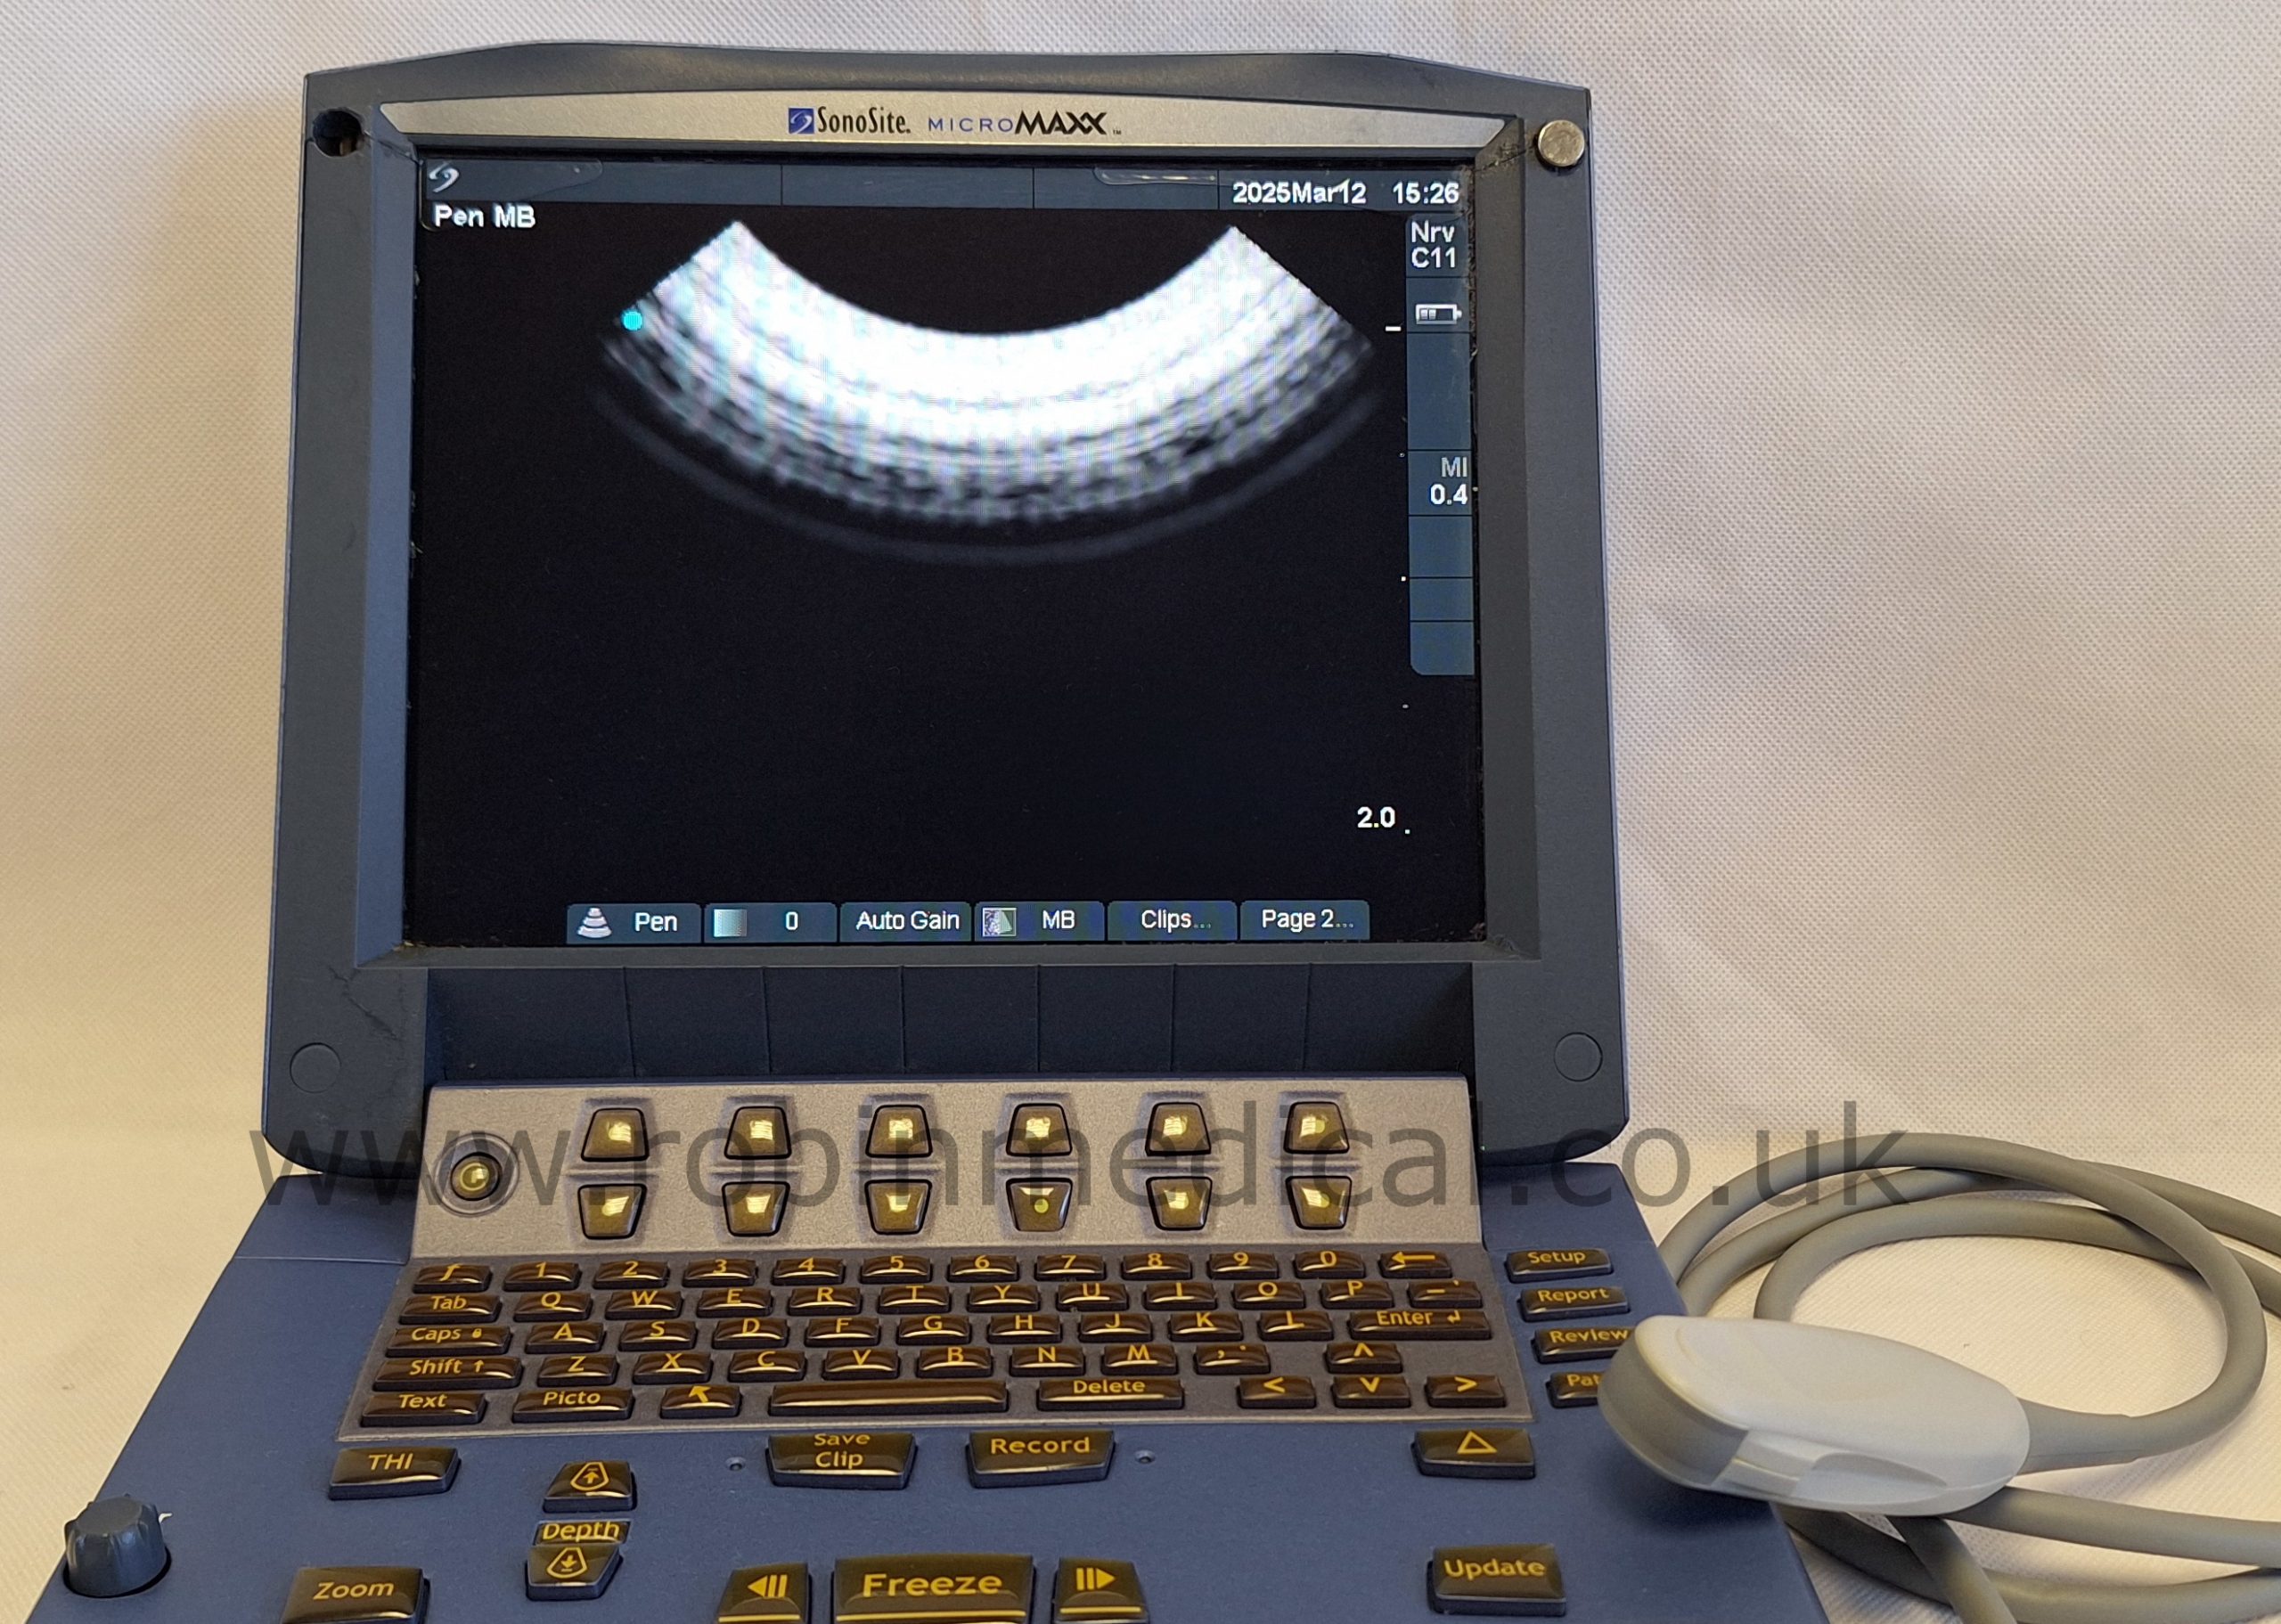

The Sonosite C11e P07161-16 is a high-performance curved-array transducer designed for the Sonosite MicroMaxx ultrasound system. With a frequency range of 8–5 MHz, it delivers exceptional imaging clarity for abdominal, pediatric, and vascular applications. Its compact 11 mm footprint makes it ideal for scanning in narrow or confined anatomical regions, while maintaining superb detail resolution. This probe offers versatility and portability in fast-paced clinical environments.

| Imaging Modes | 2D, M-Mode, Color Doppler |

The probe functions as intended and the condition is exactly as shown in images.